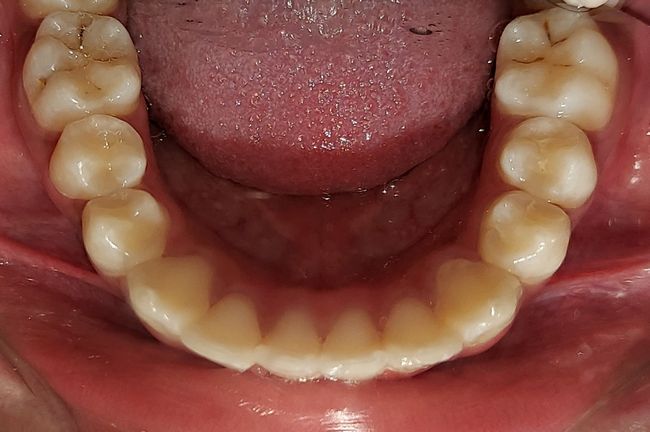

Intra-oral : Pre-treatment : Occlusal View

Intra-oral : Post-treatment : Occlusal View